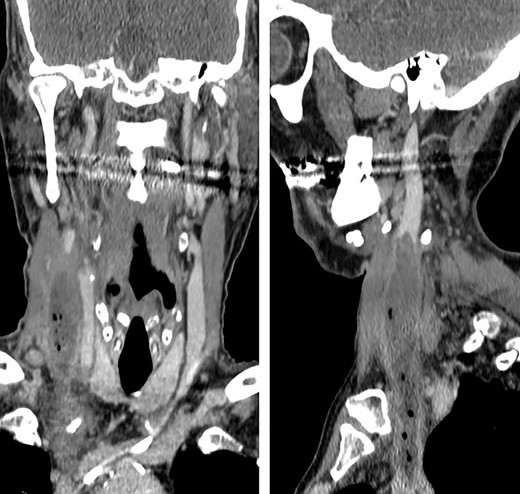

Coronal and sagittal images showing the jugular thrombosis along the neck.

Forty-eight hours later, the patient presented self-limited abdominal bleeding probably related to high dose of low molecular weight heparin (LMWH), which was treated conservatively. At the same time, hiccups appeared. It initially responded positively to haloperidol and chlorpromazine, but it progressed in frequency and intensity, becoming uncontrollable. A CT scan confirmed the absence of intraabdominal complication, and the patient was admitted to the intensive unit care to intensify hiccup treatment. During the next days, he started with fever peaks. Bacteraemia related to CVC was diagnosed, as well as inflammatory signs on the right jugular venous access. Due to the previous findings, a cervicothoracic CT was performed showing a thrombus and air bubbles into the right jugular vein. This conditioned a dilatation of an area of the vein intimately related to the phrenic nerve.

Different agents have been associated to hiccups etiology, which stimulate central or peripheral structures of the hiccups’ reflex arc [1, 2, 4]. Some of these agents, such as trauma, tumors, infections or metabolic diseases, produce persistent hiccups (lasting more of 48 hours) or even untreatable (2 or more months lasting) [1, 4]. In this patient, hiccup etiology was difficult to identify and resulted in a diagnostic challenge, because fever and cervical inflammatory signs appeared days after hiccups. When signs and symptoms came together, a cervical TC was performed, concluding that manipulation of CVC led to a septic thrombosis of internal jugular vein, its dilatation and, finally, the direct compressive stimulation of phrenic and vagus nerves (Figs. 1 and 2). Topaz et al described a case of uncontrollable hiccups after the insertion of a catheter into jugular internal vein because of the compression of phrenic nerve due to a hematoma [2, 3].